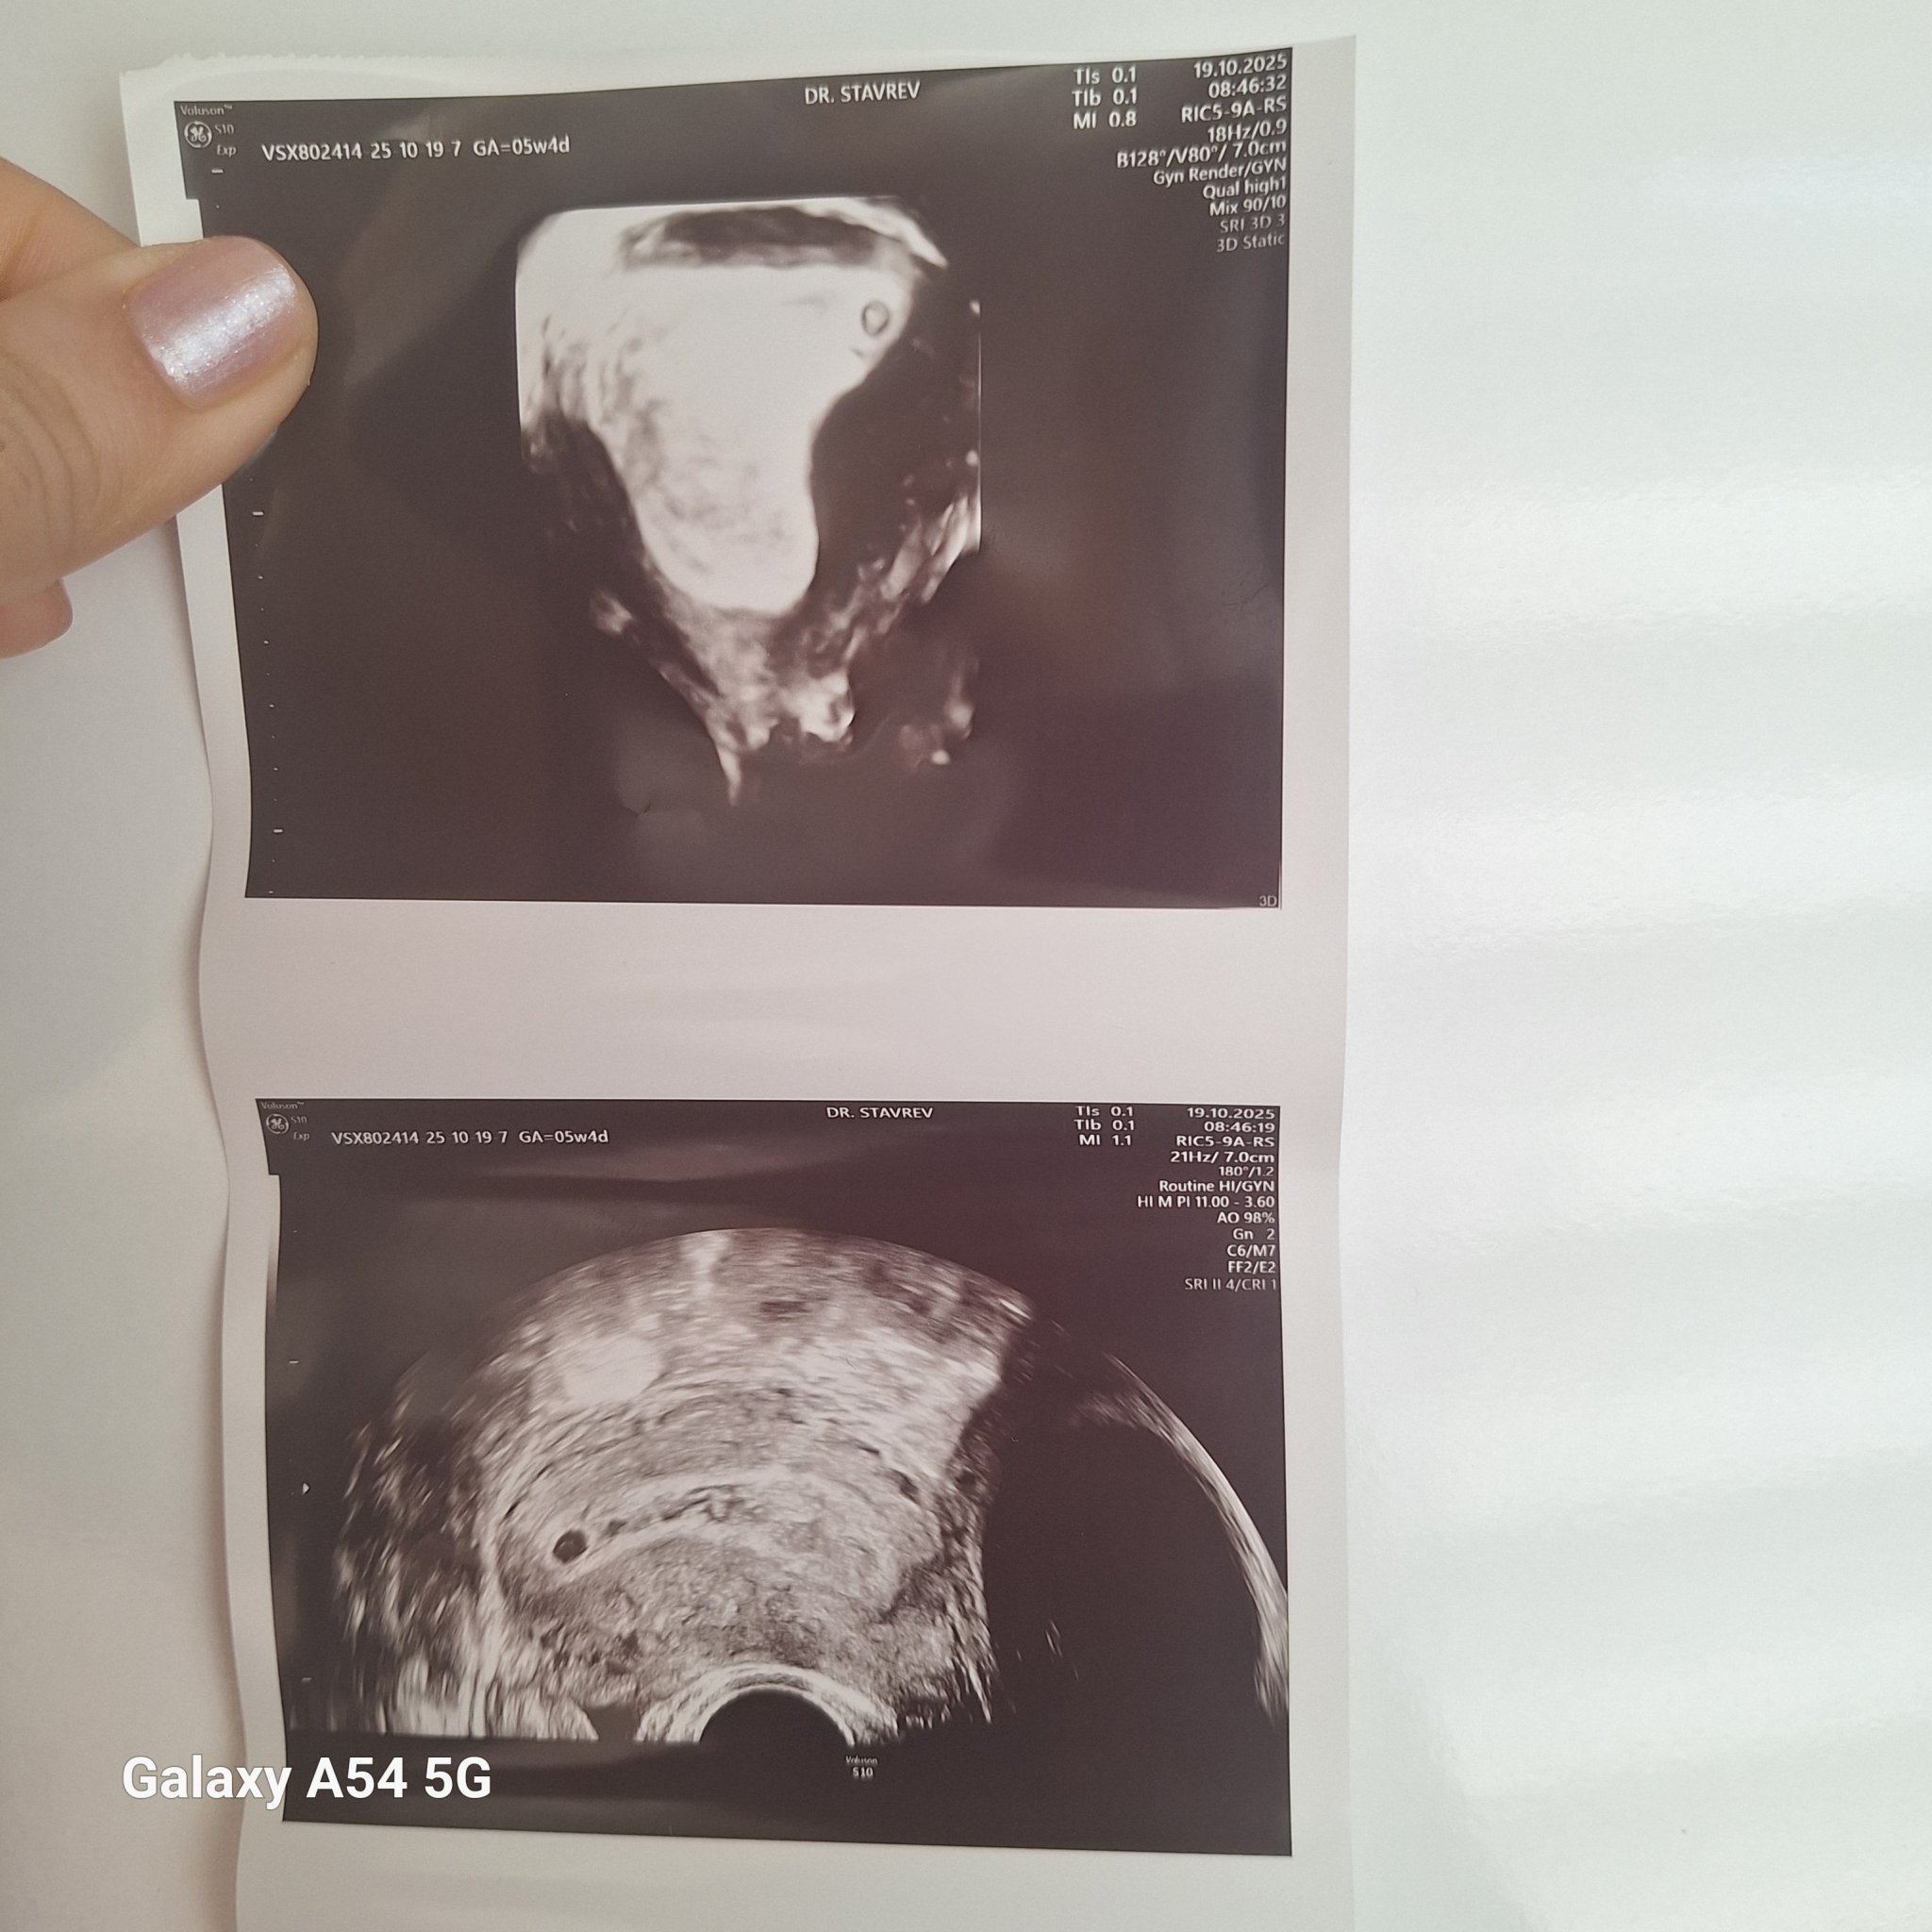

Какво представляват белите точки в плодния сак на ехографската снимка?

Какво представлява жълтото тяло на ехографската снимка?

Какво представляват черните точки в матката на ехографската снимка?